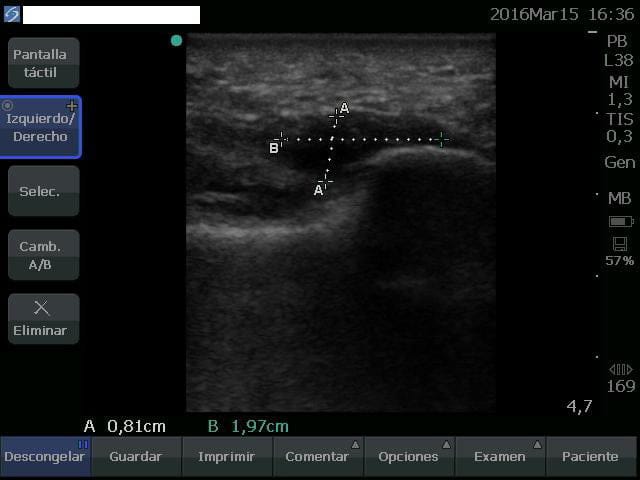

El período de recuperación en una rotura de la fascia plantar suele ser mayor al de una fascitis (inflamación) o fasciosis (degeneración). En este caso nos llevó 14 semanas hasta la vuelta a la realización de ejercicio físico de forma normal. Un período levemente por encima de lo normal debido a la gran extensión de la rotura, visible en imágen ecográfica.